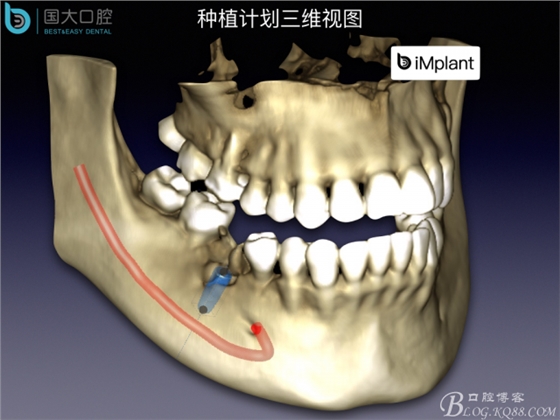

首頁牙科種植 TypeC Socket即刻種植臨床案例

TypeC Socket即刻種植臨床案例

來源于國大口腔 邵現(xiàn)紅醫(yī)生發(fā)表的博文